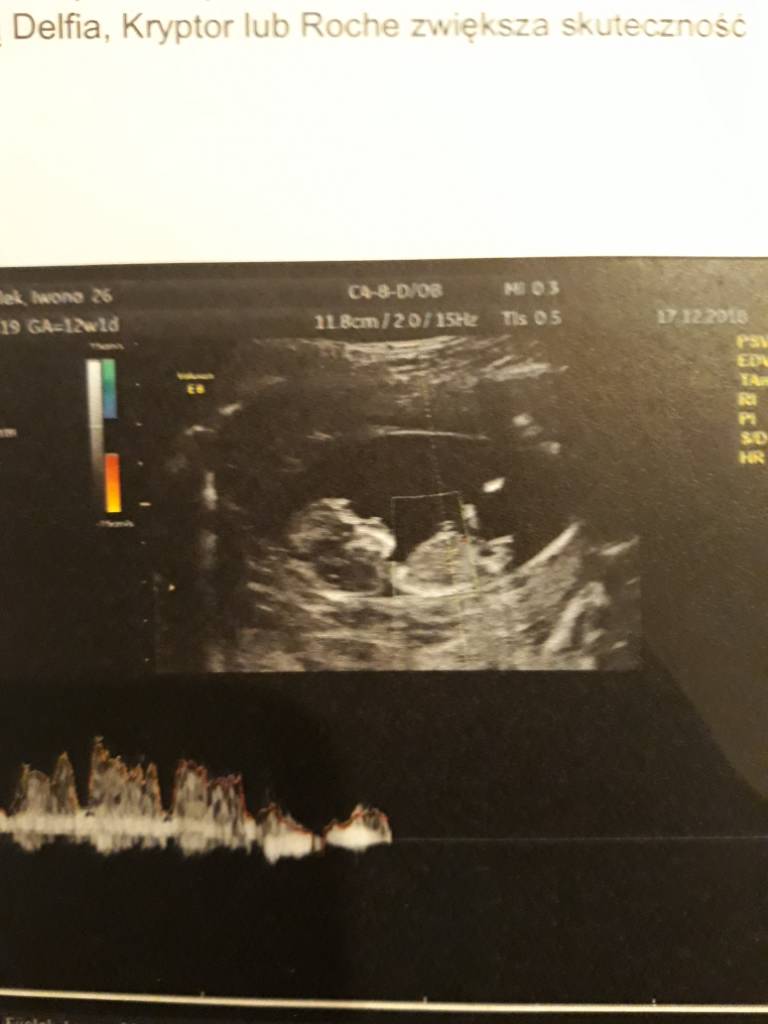

A no i dolaczam zdjecia moich Kabanoskow - jeden leniuszek ladnie pozowal a drugi wyglada jak kosmita bo sie ruszal , dzis tez do mnie machal !

A no i dolaczam zdjecia moich Kabanoskow - jeden leniuszek ladnie pozowal a drugi wyglada jak kosmita bo sie ruszal , dzis tez do mnie machal !ale z dzis zdjec nie mam bo to byl szybki.poglad ze wzgledu na upadek... aaa plecy bola ;(

Pytałam tez lekarki czy to zle ze jedno lozysko z przodu a drugie stylu i stwierdzila, ze to bardzo dobrze bo im mniej maja ze soba wspolne i sa odizolowani nawet stronami lozyska tym lepiej dla nich. Uf...Zobacz załącznik 926248Zobacz załącznik 926249Zobacz załącznik 926250Zobacz załącznik 926251Zobacz załącznik 926252